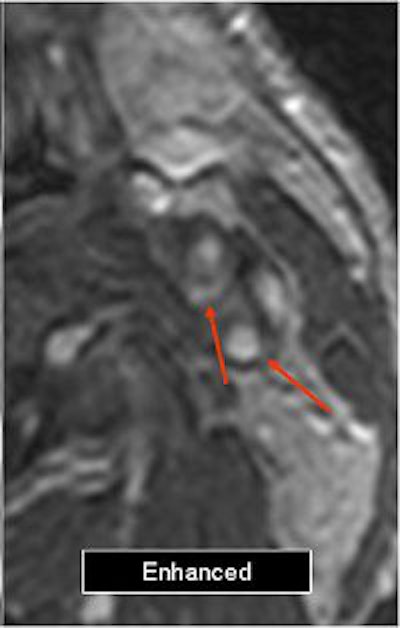

The mean score for plaque enhancement on unenhanced and enhanced images was 1.44. On subtracted images, the mean score was 2.44.

![]() |

| Above, the unenhanced image. Below, the enhanced image and the MRA showing plaque enhancement, which is more evident after electronic subtraction. All images courtesy of Dr. Francesco Sardanelli. |

"We can say that subtraction imaging is a useful tool to detect plaque enhancement," Flor said. "Plaque enhancement does not seem to correlate with the degree of stenosis as we see a large prevalence of moderate stenosis."